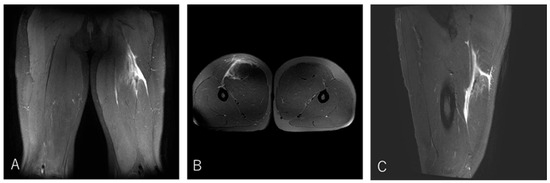

Impact of Proximal Conjoint Tendon Injury on Return to Play in the BF–ST Complex: A Prospective MRI-Based Study

by Makoto Wada, Takumi Okunuki, Takeshi Sugimoto, Yasuhito Tanaka and Tsukasa Kumai

Background/Objectives: Proximal hamstring injuries involving the biceps femoris–semitendinosus (BF–ST) conjoint tendon (CT) often exhibit delayed healing, yet the prognostic significance of CT involvement and intratendinous injury morphology has not been fully clarified. This study aimed to determine whether full-layer CT injury, particularly bilateral [...] Read more.

Background/Objectives: Proximal hamstring injuries involving the biceps femoris–semitendinosus (BF–ST) conjoint tendon (CT) often exhibit delayed healing, yet the prognostic significance of CT involvement and intratendinous injury morphology has not been fully clarified. This study aimed to determine whether full-layer CT injury, particularly bilateral involvement in Zone C, prolongs return-to-play (RTP) in competitive rugby athletes. Methods: This prospective study evaluated 41 university rugby players with acute BF–ST complex injuries using clinical examination, ultrasonography, and MRI. Injuries were classified by Type (I: full-layer CT; II: BFLH-only; III: ST-only), Zone (A–E), and Grade (0–3). RTP was defined as unrestricted return to team training or match play. Group differences were analyzed using ANOVA or non-parametric tests with appropriate post hoc corrections. Results: Type I injuries required significantly longer RTP (11.4 ± 4.8 weeks) than Type II (5.3 ± 2.4 weeks) and Type III (4.0 ± 1.7 weeks), confirming the strong impact of CT involvement on prognosis. In Zone C, bilateral full-layer CT involvement was associated with an approximately twofold longer RTP duration compared with unilateral BFLH-side injuries, indicating that intratendinous tissue disruption influences recovery. These findings highlight the importance of early MRI-based assessment to identify clinically relevant tendon involvement patterns. Conclusions: Full-layer CT injuries, particularly bilateral intratendinous patterns in Zone C, markedly prolong RTP compared with isolated BFLH or ST injuries. An MRI-based classification incorporating injury type, zone, and extent of CT involvement provides clinically valuable prognostic information and may enhance RTP decision-making. Full article

Show Figures

Figure 1